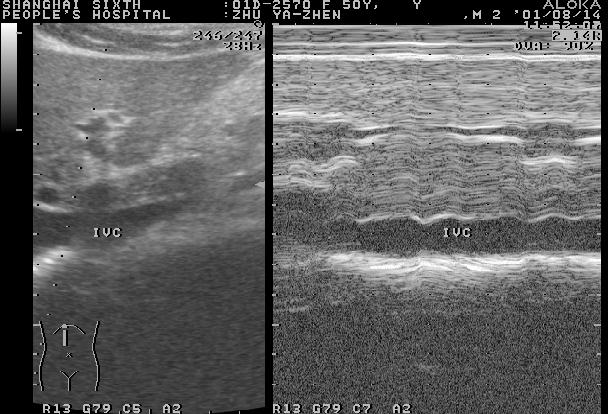

正常肝脏声像图:M型超声(右图)示靠近第二肝门附近的肝实质随心动周期变化而有伸缩,提示肝质地柔软

3、肝静脉 肝静脉与门静脉走行呈双手十指交叉状,肝静脉壁不易显示,直而柔软,管腔内血液显示清晰,血流频谱呈“W”形。